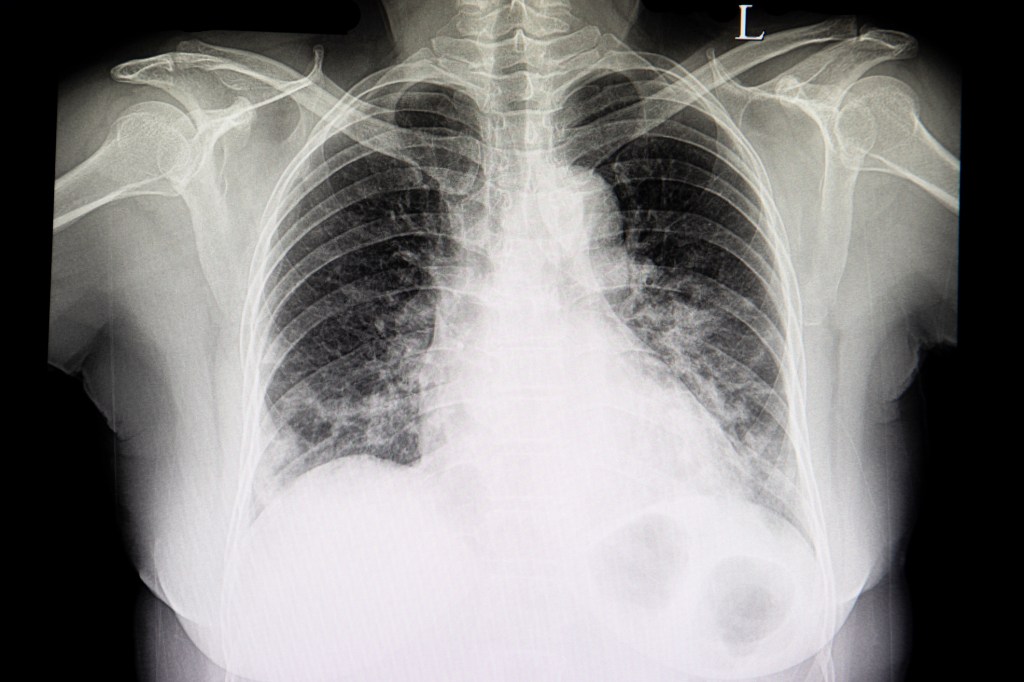

上圖為心臟衰竭患者的胸部X光,

中間白色水球形狀的是擴大的心臟,代表無力的心臟。

心臟兩側白白毛毛,像棉花的樣子,以心臟為中心,散布在兩側肺部的是水腫的肺部。

擴大的心臟,加上水腫的肺部,會造成呼吸困難,胸悶,手腳冰冷,下肢水腫,疲倦,食慾不振…等症狀。